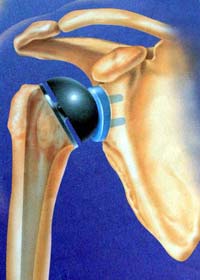

骨性关节炎造成的肩关节软骨破坏,骨刺形成 肱骨头粉碎骨折

全肩关节置换术后示意图 肱骨头置换后X线片